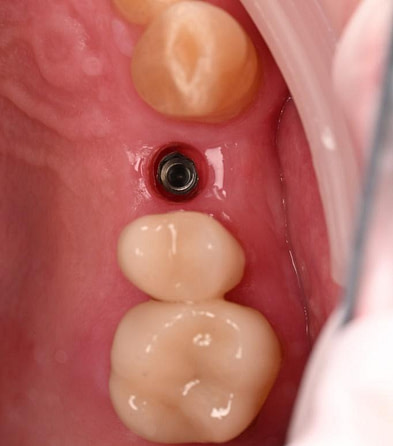

Three months after the implant surgery, a thorough post-operative assessment revealed excellent healing and implant stability.

Digital impressions were captured using the TRIOS 4 intraoral scanner, and the implant-supported crown was designed using 3Shape Design Studio.

Implant detection matches the scan body in the intraoral scan with the digital library. A colour scale is given to show the accuracy of the matching (Green is good).